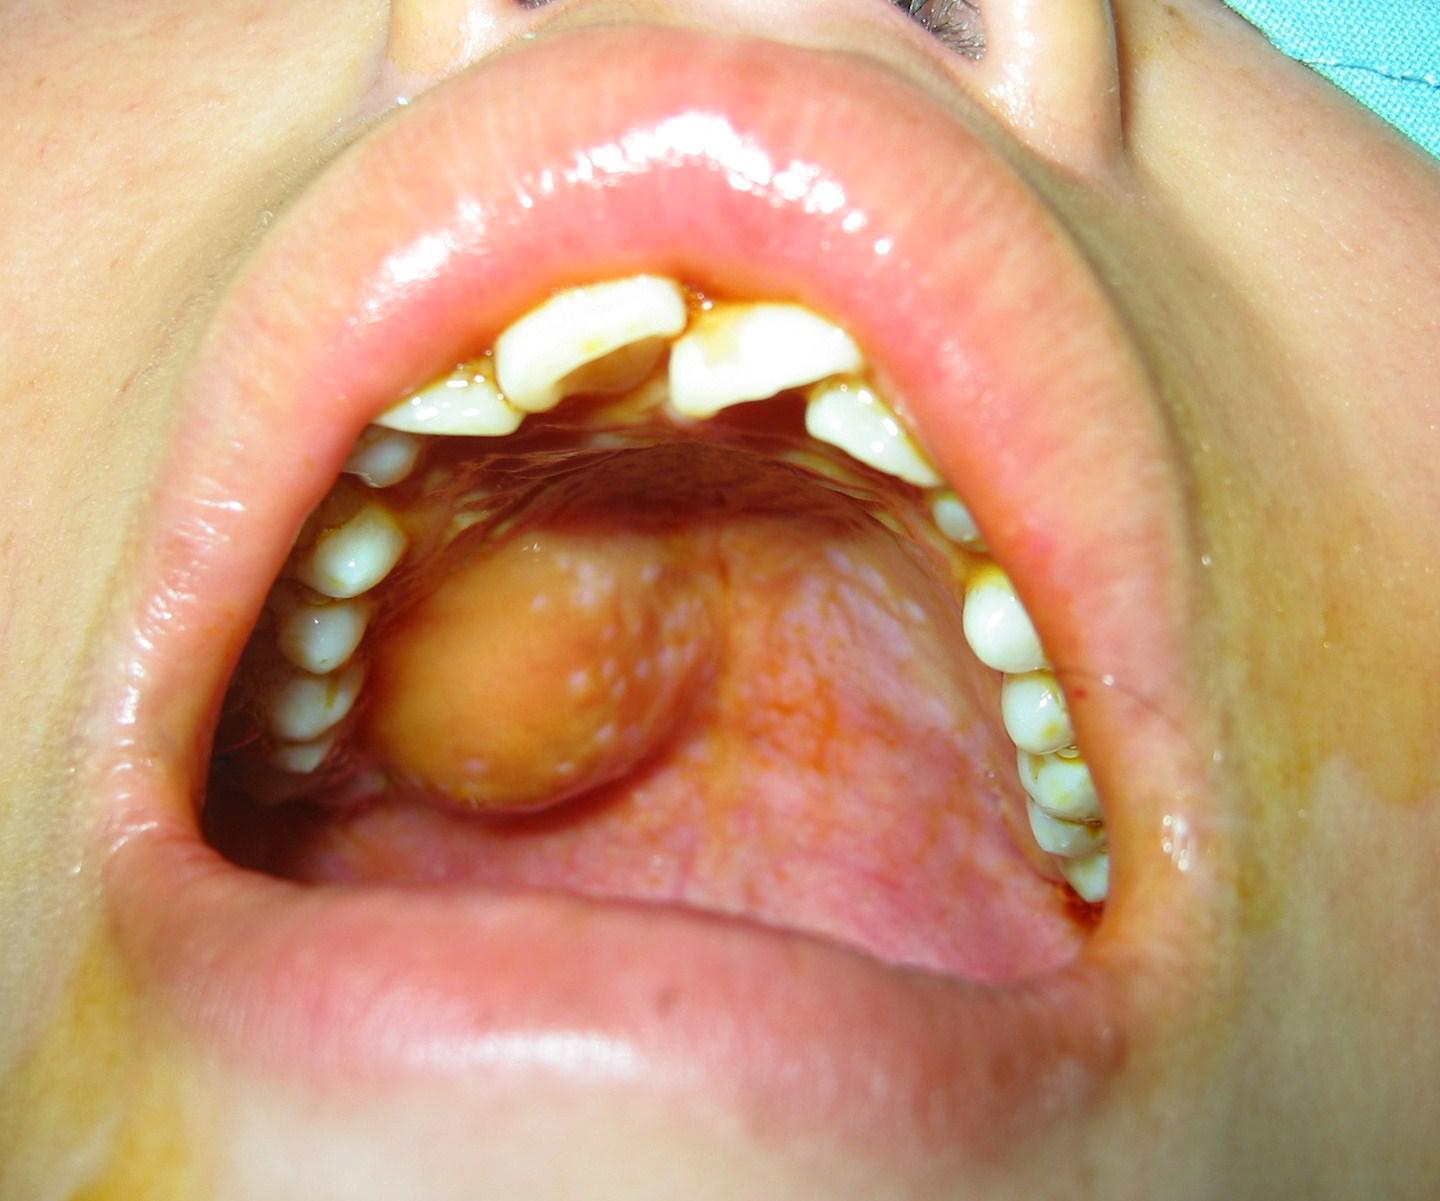

舌部咬伤清创缝合

口腔颌面部软组织咬伤

经初步检查诊断,患儿舌头咬伤,前端正中部可以看到一个3厘米的横形